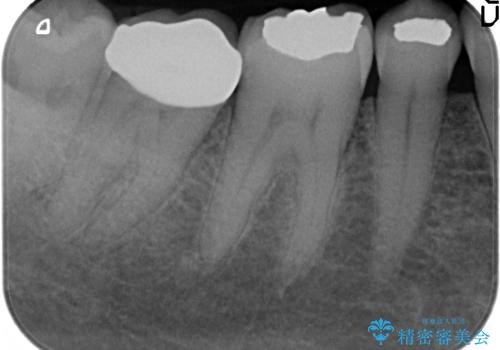

- 右下7の銀歯が外れてしまった方の症例です。

古い樹脂やカリエスを除去後、形を整え、オールセラミッククラウンによる補綴を行いました。